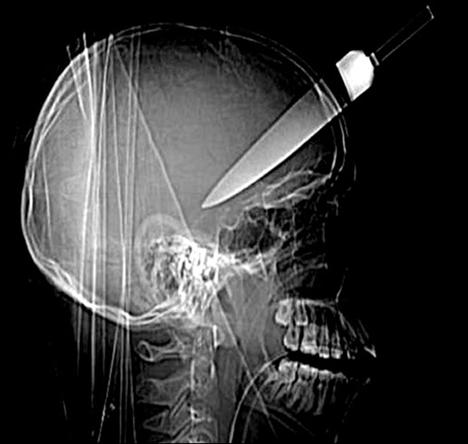

Şoke eden röntgen filmleri

Bu röntgen filmleri görenleri şaşkına çeviriyor!